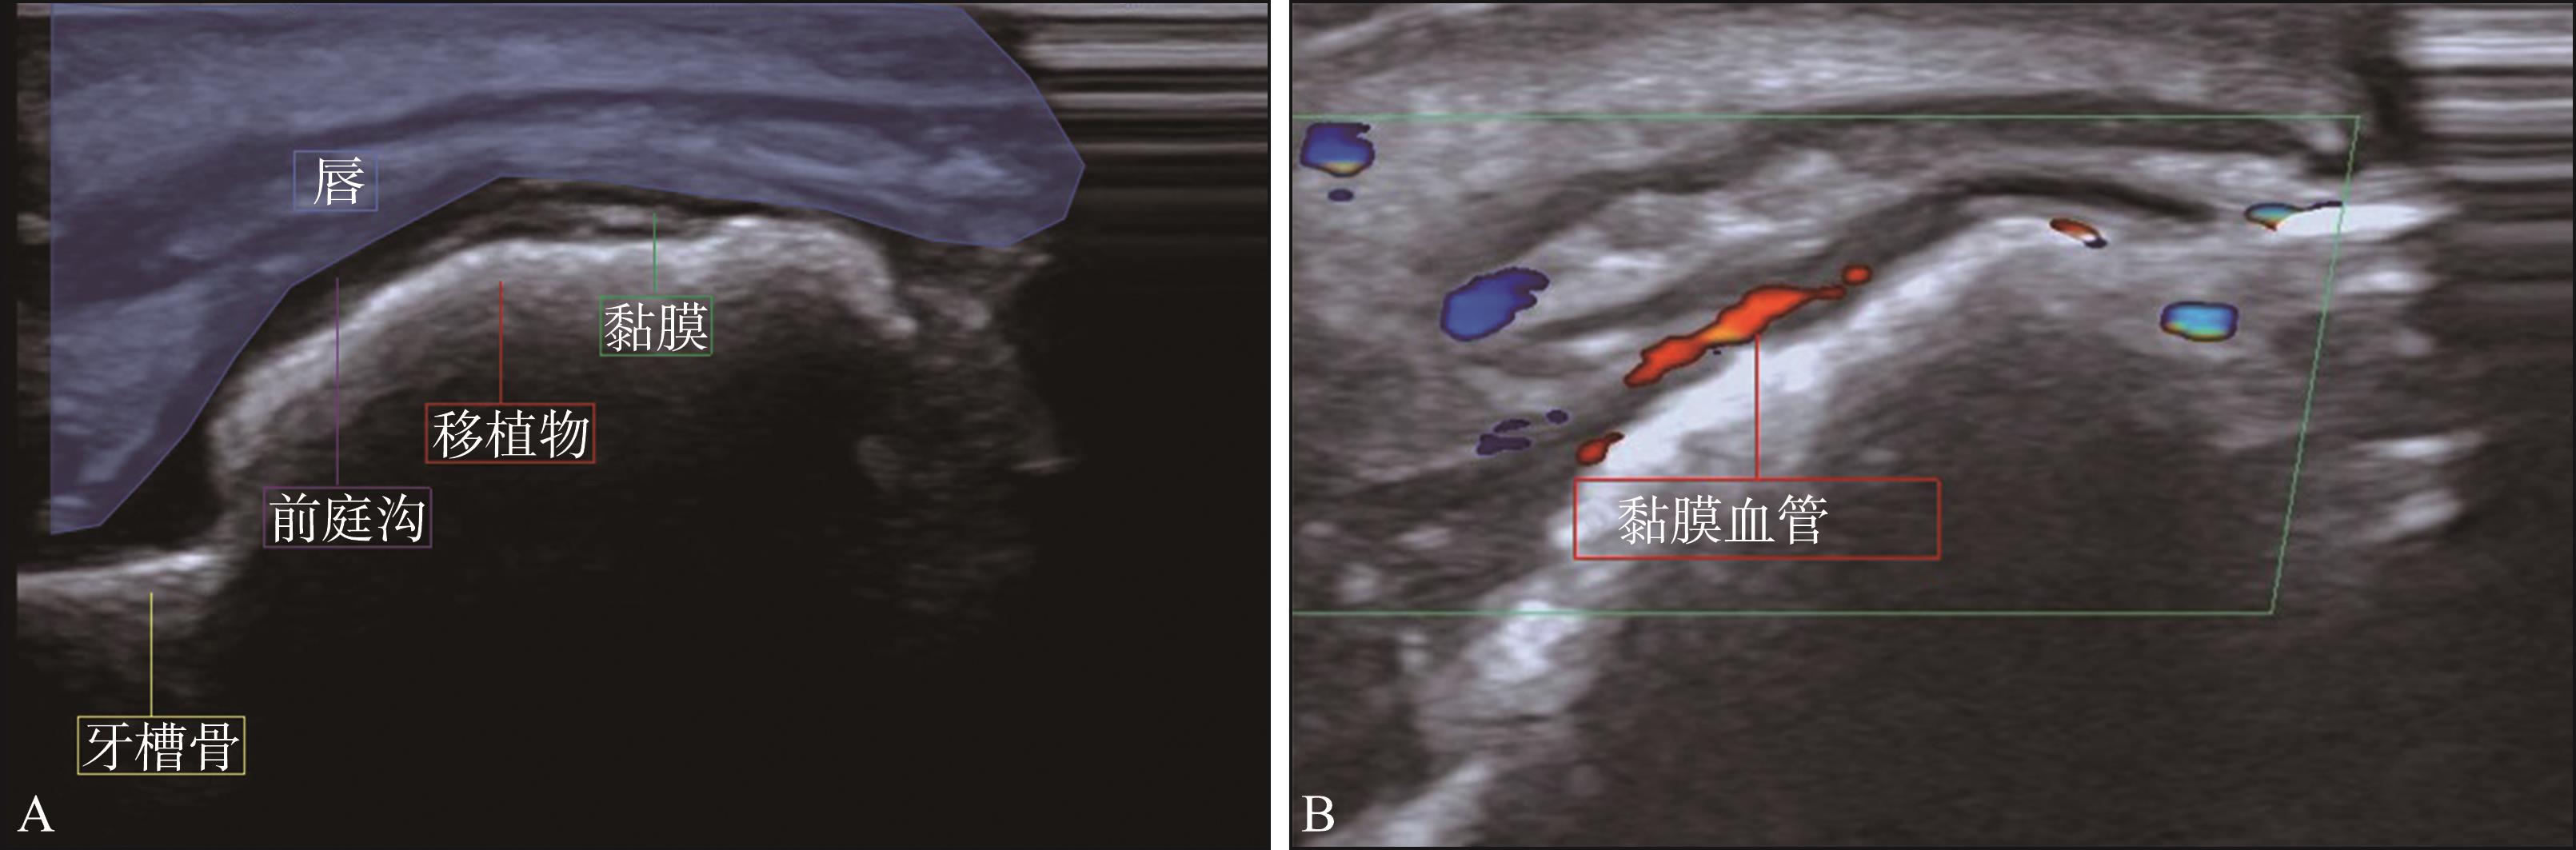

Xue F, Wu BZ, Zhang R, et al. Analyses of gingival papilla blood flow via color doppler flow imaging and micro-flow imaging in patients with advanced periodontitis: a clinical pilot study[J]. Eur J Med Res, 2024, 29(1): 527.